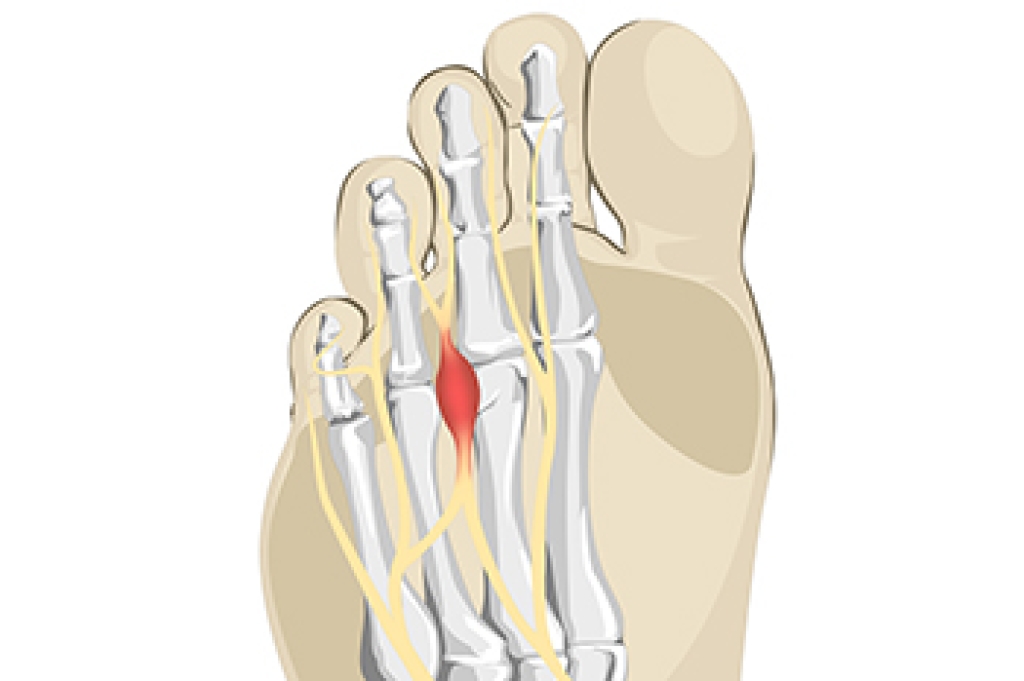

Arthritis in the feet is a condition that can bring a range of discomforts and unique sensations. It often manifests as pain and stiffness in the joints, making every step a potential challenge. Individuals with foot arthritis may experience a deep, aching pain that worsens with movement. This discomfort can be present in various areas of the foot, including the toes, the midfoot, or the ankle. One common sensation associated with foot arthritis is a feeling of stiffness or inflexibility. It can be particularly pronounced in the morning or after periods of inactivity. As arthritis progresses, swelling and warmth may accompany the pain, making the affected foot feel tender to the touch. In more advanced cases, individuals may notice a grinding or popping sensation in the affected joints, indicating the wear and tear of the cartilage. Understanding what arthritis in the feet feels like is essential for timely diagnosis and effective management. If you have any of the above symptoms which may indicate arthritis in the feet, it is suggested that you schedule an appointment with a podiatrist who can guide you toward relief methods.

- Swelling

- Pain

- Stiffness

- Decreased Range of Motion